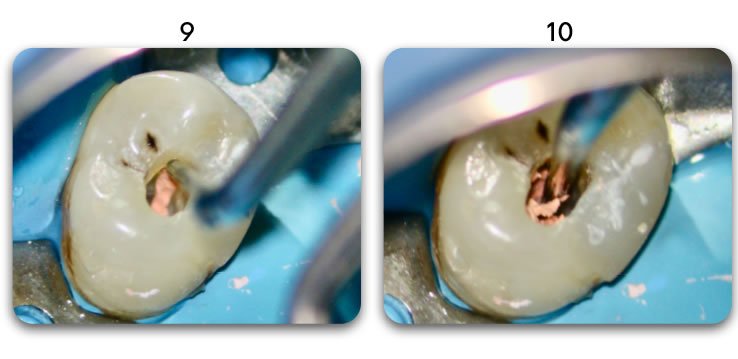

Template for x-rays

Biolight® DRILL-FREE posts are available in bundles of 4, 6, 9 and 12 strands. The post size is selected based on the width of the canal at the coronal area. Depending upon the canal width at the apical stop, a certain number of strands must be pushed to the stop. Both of the measurements are made with the assistance of a radiograph and the template that is included in the TRAINING KIT.